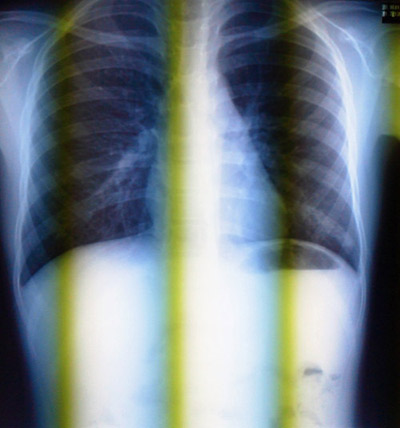

![]() |

やっぱりマイコだったよ。 |

X線、撮って確認しとこうか。

うん、キレイになった。 |

あと5日分、抗菌剤を追加しておく。

月曜から学校に行っていいよ。

と、お墨付きを頂いた。